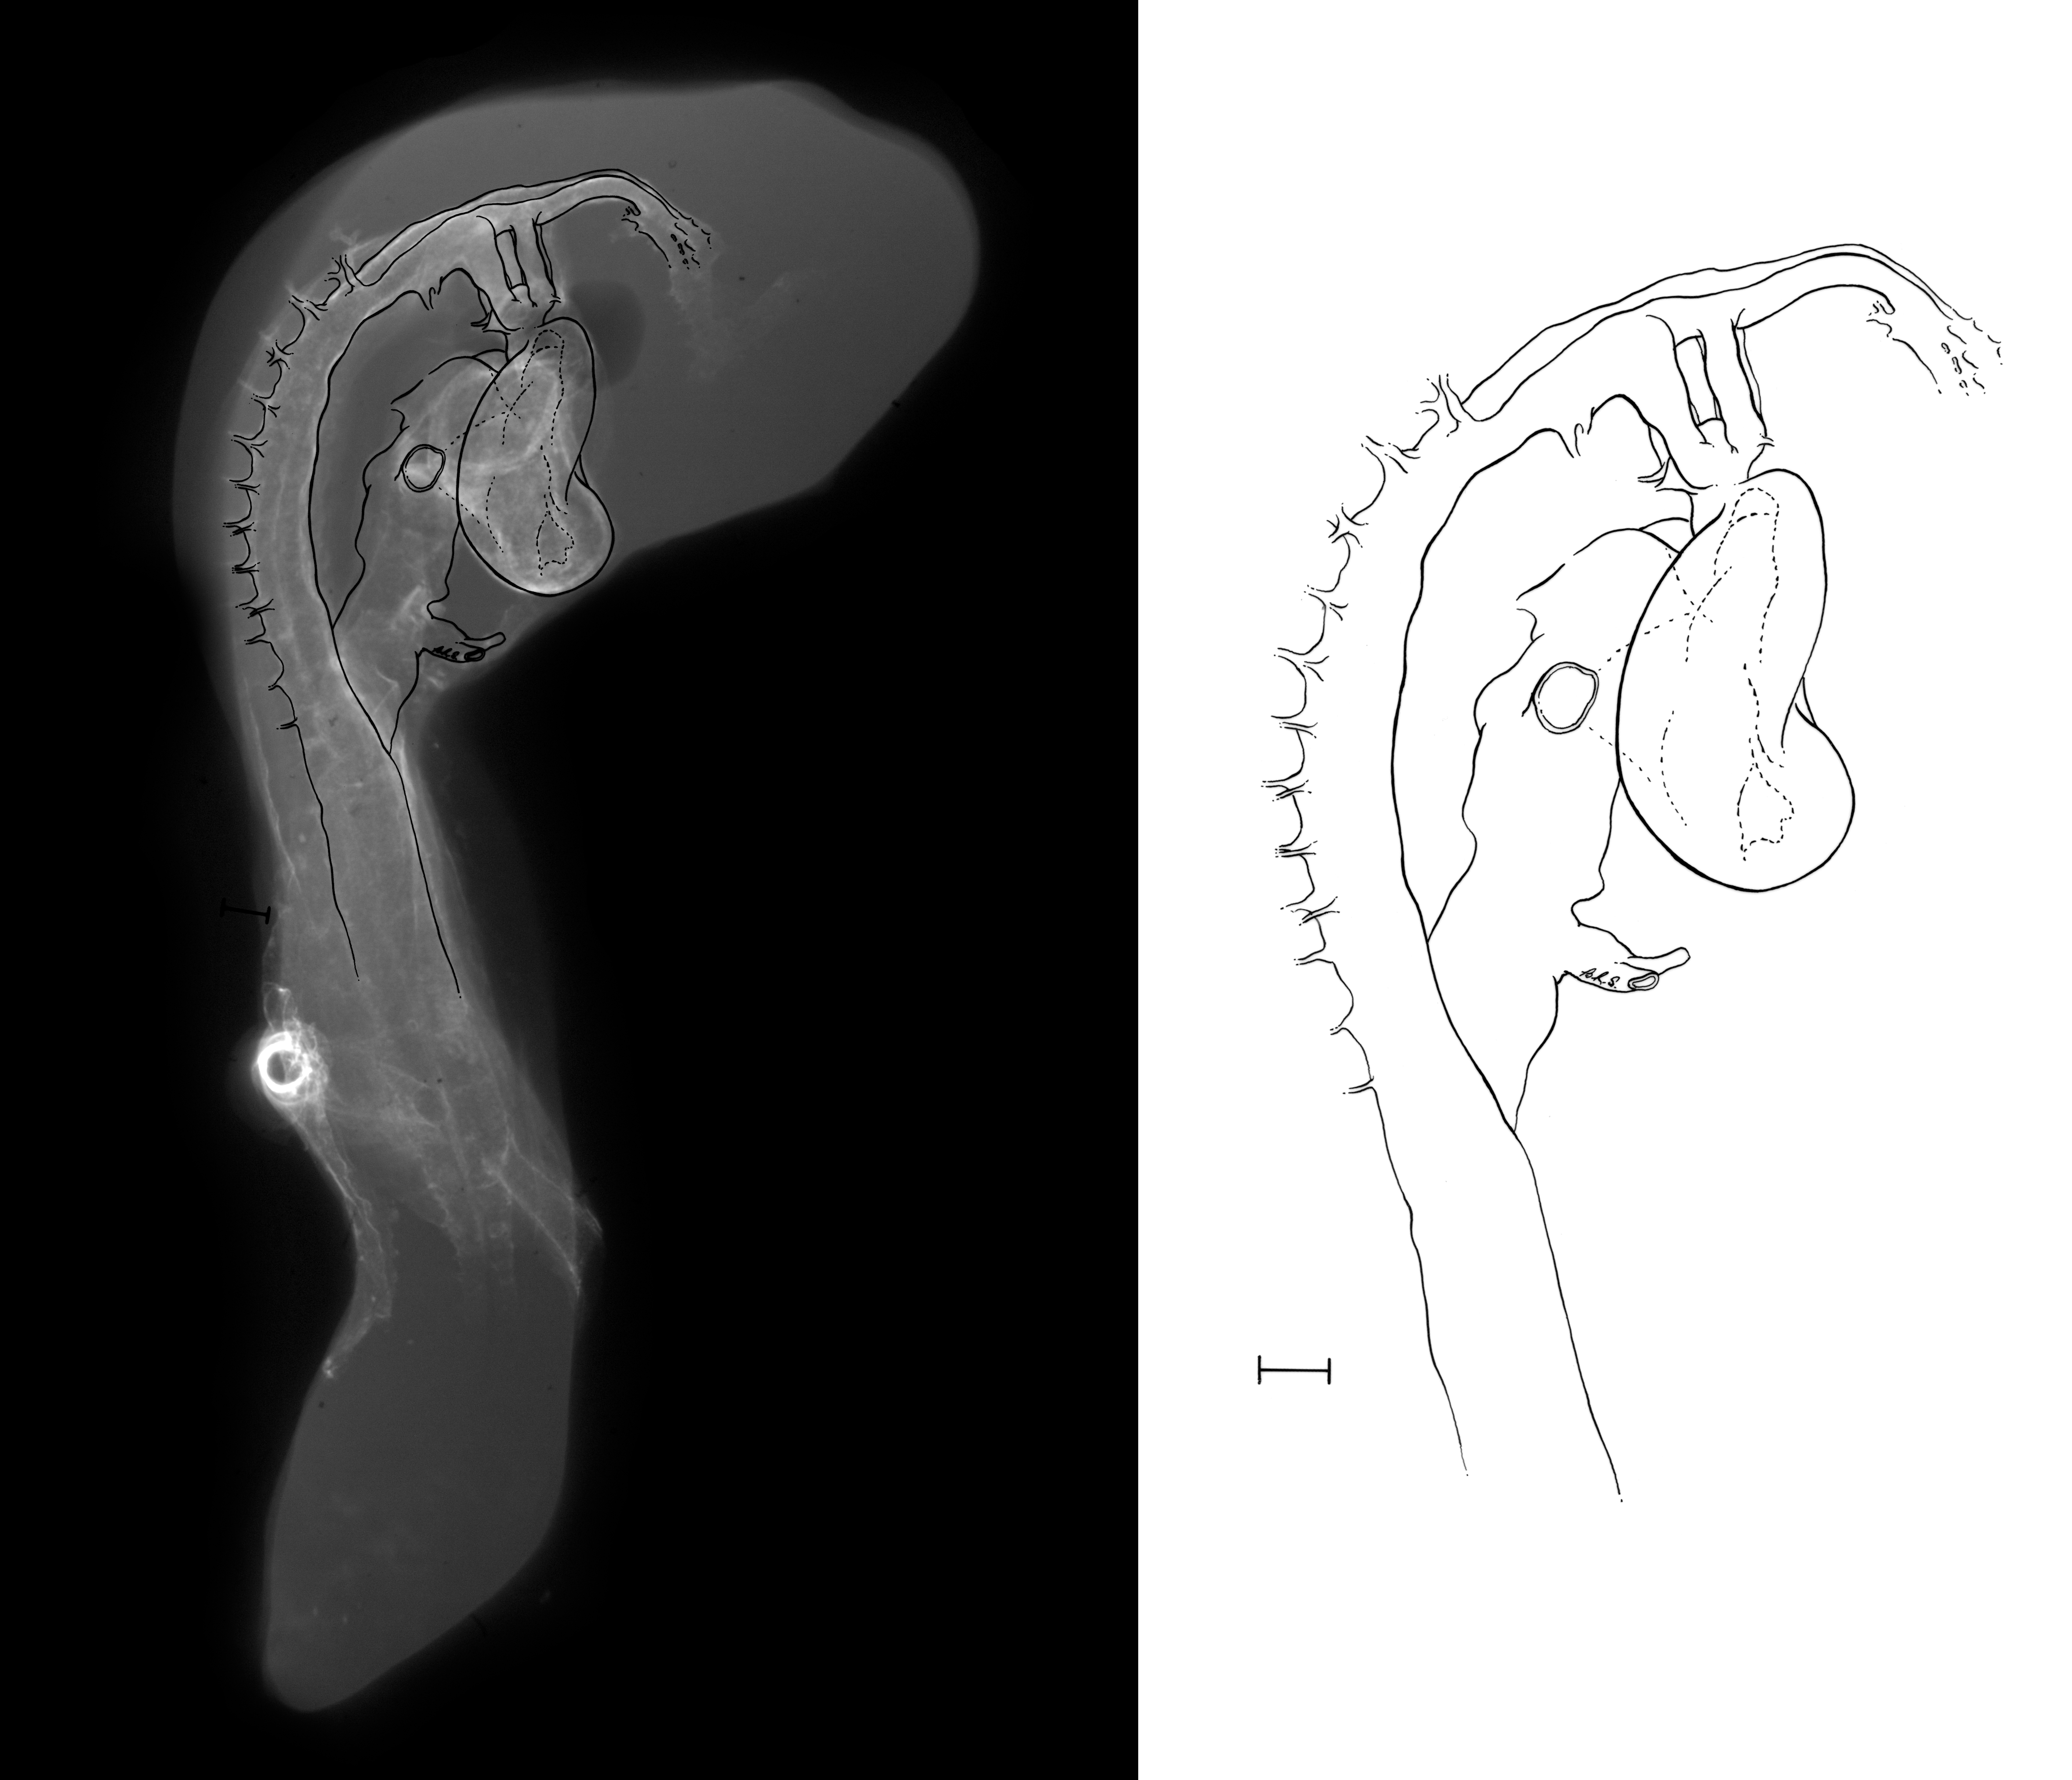

Chick Embryo Microangiography

Hamburger-Hamilton (HH) Stage 16 (approx. 2.1 - 2.5 days)

Drawing